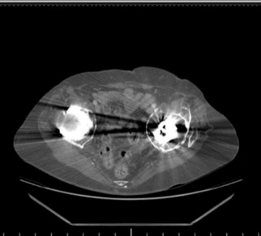

Advanced Imaging

Given the complexity of the defect and the need for meticulous preoperative planning, a computed tomography (CT) scan with 3D reconstructions was indispensable.

* CT findings: Confirmed severe Paprosky type IIIb acetabular bone loss, characterized by:

* Complete loss of the superior dome.

* Discontinuity of the anterior and posterior columns in segments.

* A large contained cavitary defect with an uncontained segmental defect superiorly.

* The medial wall was largely intact but severely thinned, with evidence of medial protrusion of the polyethylene liner.

* The femoral head allograft used in the previous revision showed patchy integration with areas of non-union and resorption, failing to provide adequate structural support.

* 3D reconstructions clearly delineated the extent of the superior and posterosuperior wall deficiencies, crucial for planning the appropriate cage and bone graft construct. They also helped to identify the remaining host bone available for screw fixation.